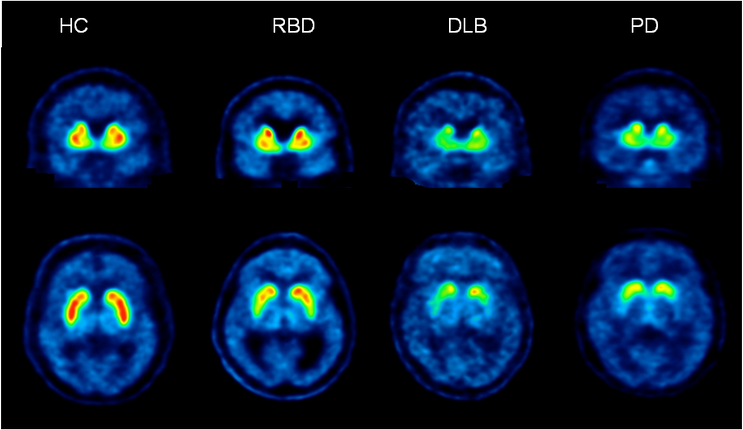

In a study published in Neurology, lead researcher Professor Barnham and colleagues describe how a known biomarker called F-AV-133 can be used with positron emission tomography (PET) scans to diagnose Parkinson’s disease and accurately track neurodegeneration.

In the Melbourne study, Florey Professor Chris Rowe and his team at Austin Health scanned 26 patients with Parkinson’s disease, a control group of 12 people, and 11 people with Rapid Eye Movement sleep behaviour disorder (RBD) which is a strong indicator of the disease.

by contrast, the PET scans showed “significant neuronal loss” in three key regions of the brain in individuals with the disease, suggesting F-AV-133 is a more sensitive means of monitoring neurodegeneration than what is now available.